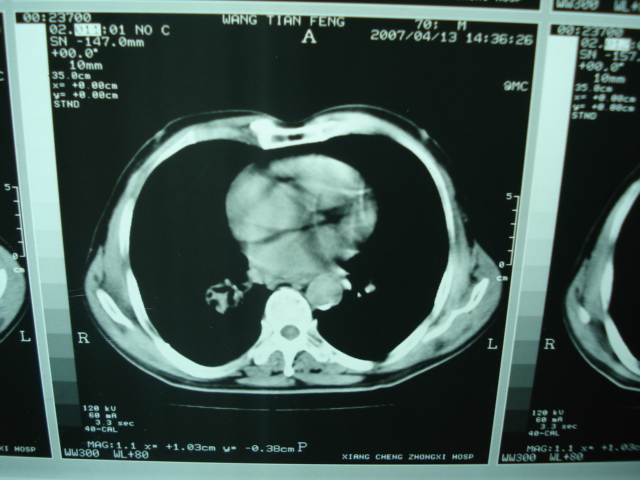

以下是引用狙击手在2007-4-18 20:17:00的发言:[br]原:2007/1/22号ct片:右肺上叶可见片状、云雾状高密度影,右肺上叶后段可见三角形高密度影,尖端指向肺门,右肺上叶后段支气管壁不规则增厚,管腔不规则增厚,纵隔未见肿大淋巴结.[br] 今ct:右肺上叶片状影增大,右肺上叶后段不张及右肺上叶后段支气管壁不规则增厚未见变化,右肺下叶背段支气管壁不规则增厚.[br] 如果考虑肺结核,但从临床证据看竟然没有一项支持肺结核,不知患者是否已经过正规抗结核治疗。没有的话,3个月了前后片看起来变化不大,似乎有不太符合肿瘤征象,不知患者是否抗炎治疗过,下叶支气管增粗还是要高度警惕,同意楼主意见,将常规病理,生化检查再做一遍。[br]

以下是引用狙击手在2007-4-18 20:17:00的发言:[br]原:2007/1/22号ct片:右肺上叶可见片状、云雾状高密度影,右肺上叶后段可见三角形高密度影,尖端指向肺门,右肺上叶后段支气管壁不规则增厚,管腔不规则增厚,纵隔未见肿大淋巴结.[br] 今ct:右肺上叶片状影增大,右肺上叶后段不张及右肺上叶后段支气管壁不规则增厚未见变化,右肺下叶背段支气管壁不规则增厚.[br] 如果考虑肺结核,但从临床证据看竟然没有一项支持肺结核,不知患者是否已经过正规抗结核治疗。没有的话,3个月了前后片看起来变化不大,似乎有不太符合肿瘤征象,不知患者是否抗炎治疗过,下叶支气管增粗还是要高度警惕,同意楼主意见,将常规病理,生化检查在做一遍。[br]